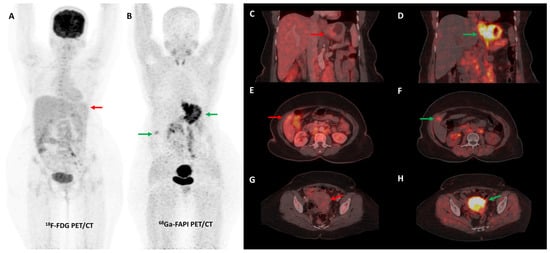

Activation of CAFs, particularly in the early development phase, leads to FAP overexpression both in tumor cells and the surrounding stromal component in CRC and other GI malignancies [72]. A higher degree of FAP expression is associated with higher tumor grade, invasiveness, and poor prognosis in CRC [73]. The first real-world clinical experience with FAP-targeted PET imaging (using either [68Ga]Ga-FAPI-04 or [68Ga]Ga-FAPI-46) in lower GI tract malignancies was reported by a German group. They found significant tracer uptake in anal cancer and liver metastases, with the TBR of most lesions being greater than 3. TNM staging was altered in 50% of the treatment-naïve patients and additional findings were picked up in 47% of patients with metastases. FAPI PET/CT improved TVD in a majority of patients being planned for radiotherapy (RT) [74]. Kömek et al. performed a head-to-head comparison of [68Ga]Ga-FAPI-04 and FDG PET/CT in 39 CRC patients. They found that FAPI PET/CT had higher sensitivity and specificity in the detection of primary lesions and lymph nodal metastases [75]. Pang et al. compared the diagnostic performance of [68Ga]Ga-FAPI-04 and FDG PET/CT in 35 patients with CRC, gastric and duodenal cancers. Overall, FAPI PET/CT had better sensitivity than FDG PET/CT for the detection of primary tumors (100% vs. 53%, respectively, p = 0.004), nodal (79% vs. 54%, p = 0.001), and distant metastases (89% vs. 57%, p = 0.001). FAPI PET/CT led to upstaging of the clinical TNM stage in 21% of the treatment-naïve patients [76]. Lin et al. reported the additional utility of [68Ga]Ga-FAPI-04 PET/CT in monitoring response to treatment in gastric carcinoma [77]. One such demonstrative case of gastric cancer is presented in Figure 3 and Figure 4.

Figure 3.

FDG and [68Ga]Ga-FAPI-04 PET/CT images in a 42-year-old woman with biopsy-proven gastric adenocarcinoma. The primary lesion in the stomach showed no abnormal FDG uptake ((A,C)—red arrows) with intense [68Ga]Ga-FAPI-04 tracer avidity ((B,D)—green arrows). FAPI PET/CT revealed a tracer avid hypodense lesion in segment V of the liver ((B,F)—green arrows), which was not picked up on FDG PET/CT ((E)—red arrow), leading to upstaging of disease. Additionally, the uterus showed no abnormal FDG uptake ((G)—red arrow) but had diffuse intense FAPI uptake ((H)—green arrow), which was interpreted as physiologic/benign uptake.

Figure 4.

Incremental role of [68Ga]Ga-FAPI-04 PET/CT over FDG PET/CT in a 42-year-old woman with metastatic gastric adenocarcinoma for post-chemotherapy response assessment. Baseline (A) and follow-up (C) FDG PET/CT scans did not reveal significant abnormal tracer uptake in the primary and metastatic lesions. Baseline [68Ga]Ga-FAPI-04 PET/CT (B) showed tracer avid gastric primary (green arrow), abdominal lymph nodes (orange arrow), and solitary liver metastasis (red arrow). Post-chemotherapy [68Ga]Ga-FAPI-04 PET/CT (D) demonstrated minimal tracer avidity in the gastric primary (green arrow) with resolution of tracer avidity in the abdominal lymph nodes (orange arrow) and liver lesion (red arrow), suggesting a favorable response to treatment.